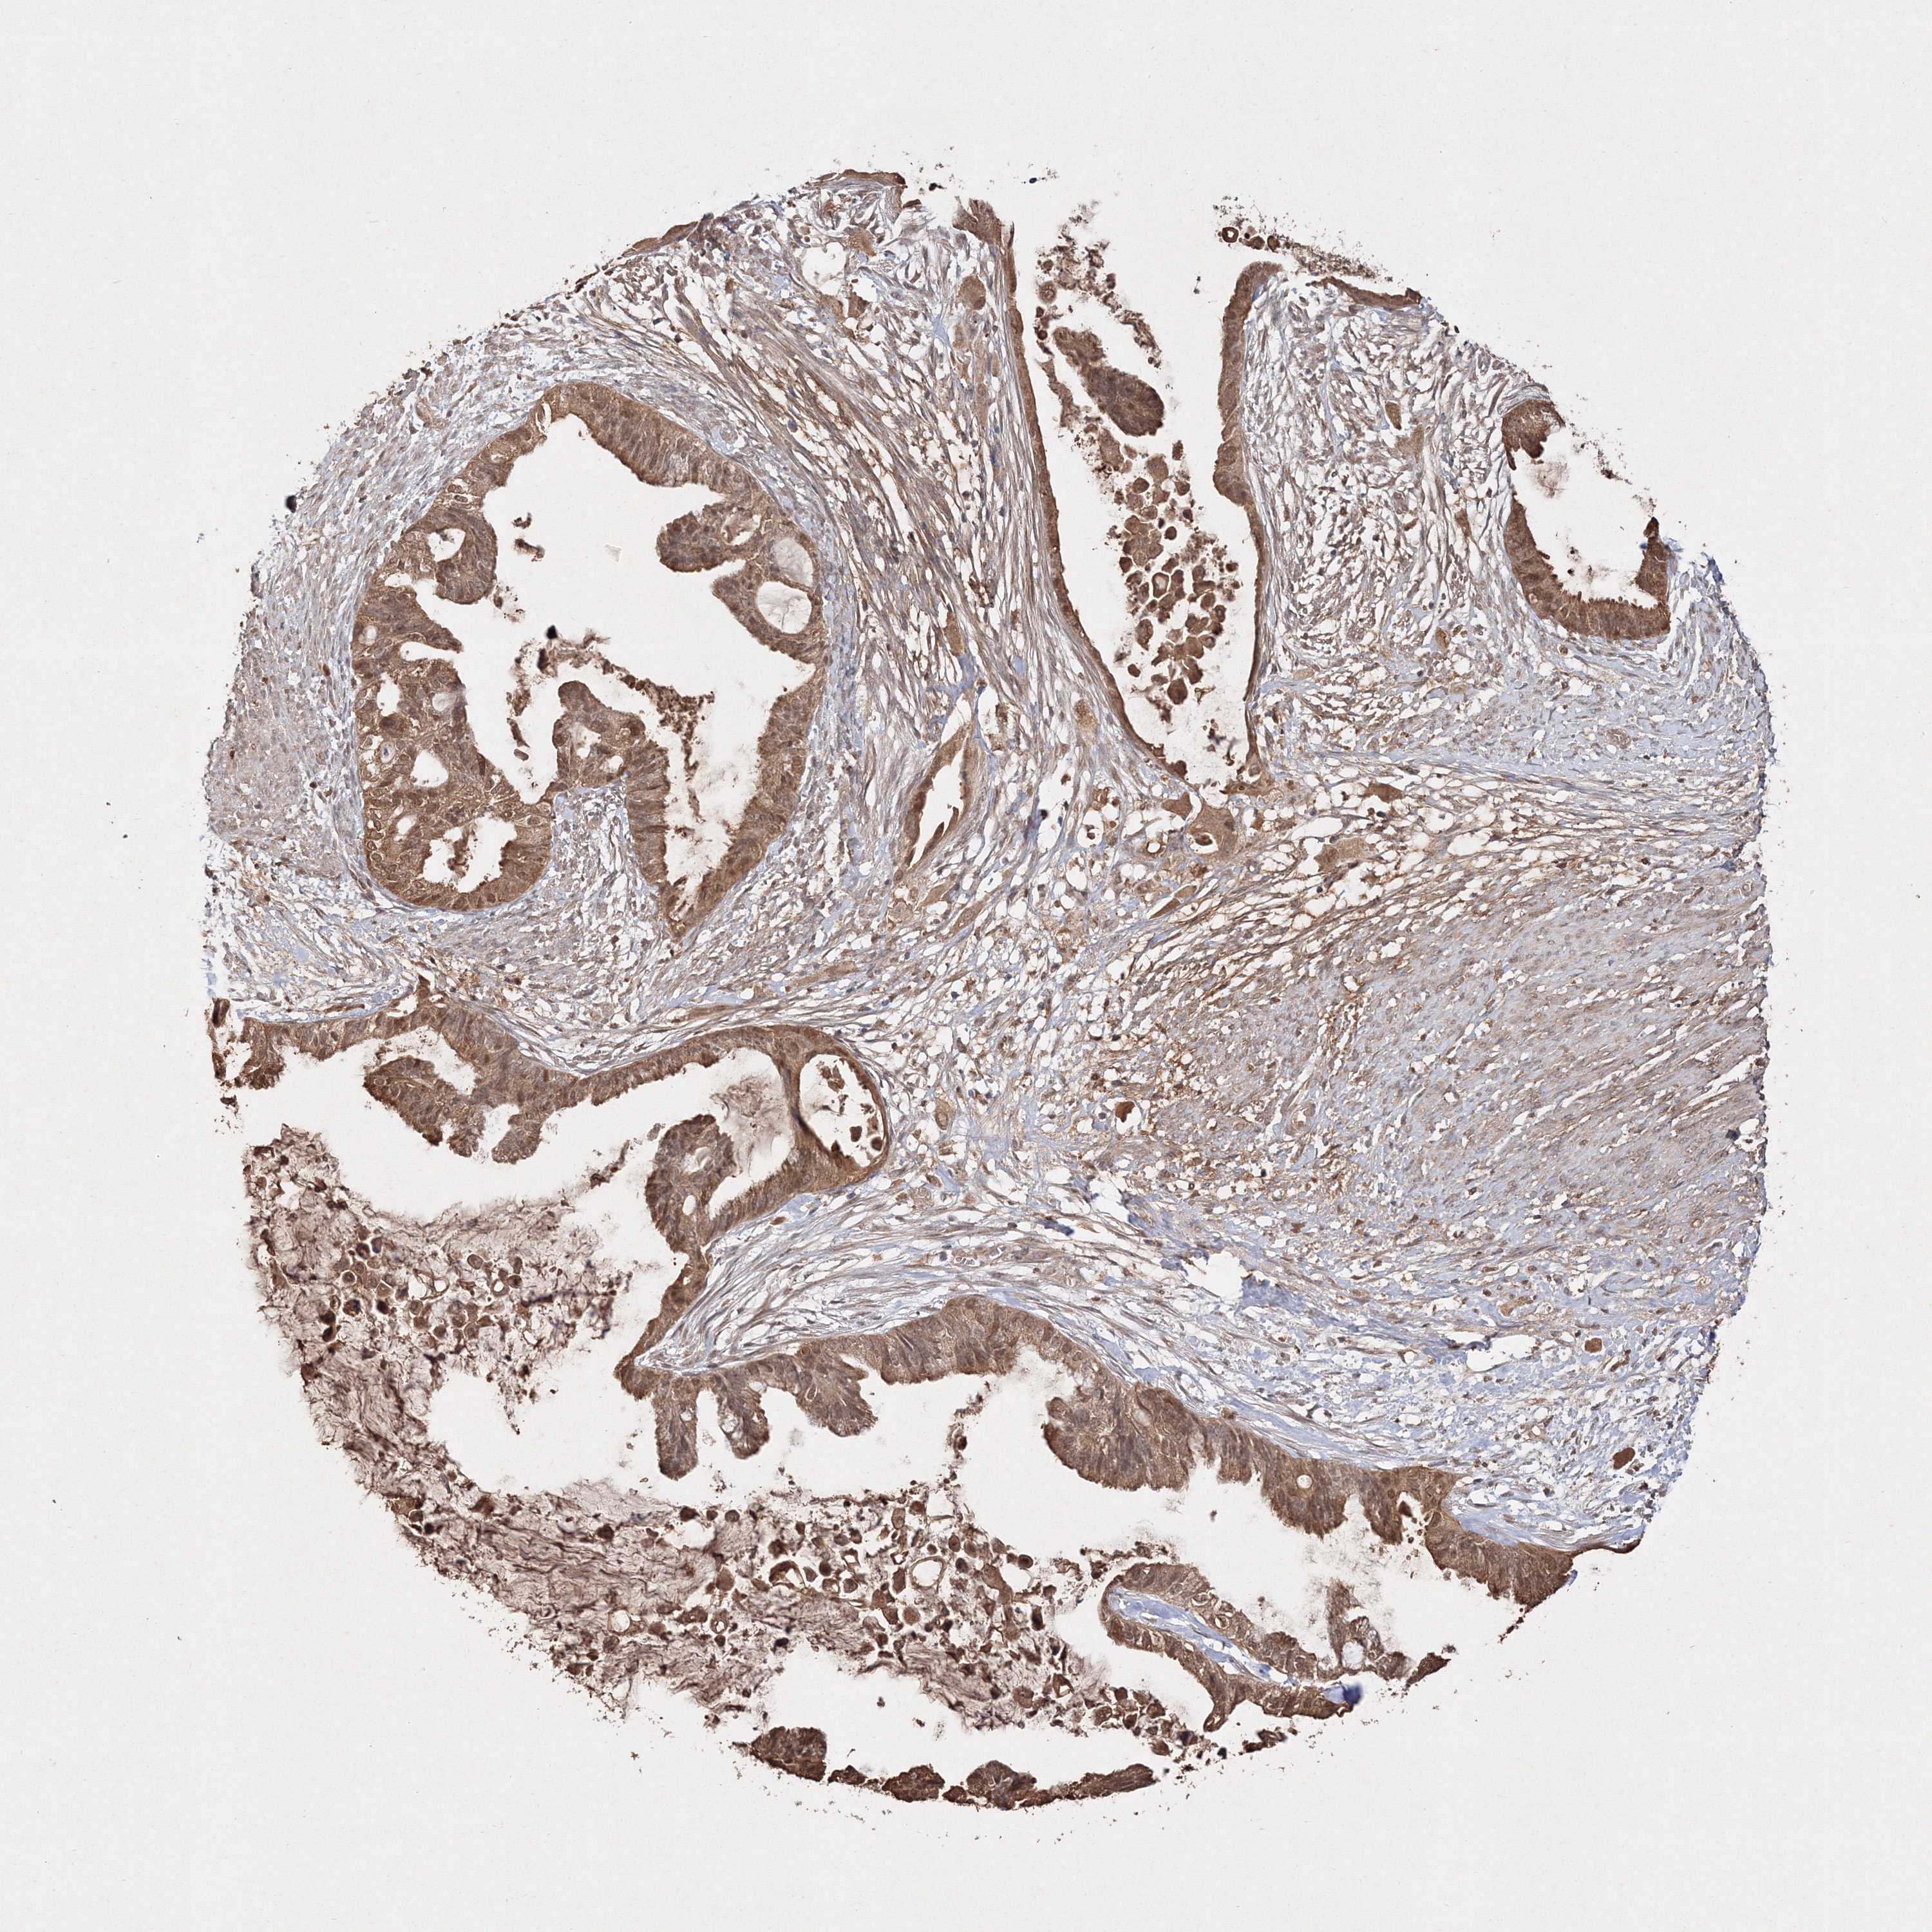

CERVICAL CANCER - Protein expressioni

A mouse-over function shows sample information and annotation data. Click on an image to view it in a full screen mode. Samples can be filtered based on level of antibody staining by selecting one or several of the following categories: high, medium, low and not detected. The assay and annotation is described here.

Note that samples used for immunohistochemistry by the Human Protein Atlas do not correspond to samples in the TCGA dataset.

Antibody stainingi

Antibody staining in the annotated cell types in the current human tissue is reported as not detected, low, medium, or high, based on conventional immunohistochemistry profiling in selected tissues. This score is based on the combination of the staining intensity and fraction of stained cells.

Each image is clickable and will lead to virtual microscopy that enables deeper exploration of all samples and also displays staining intensity scores, fraction scores and subcellular localization as well as patient and tissue information for each sample.

Adenocarcinoma, NOS